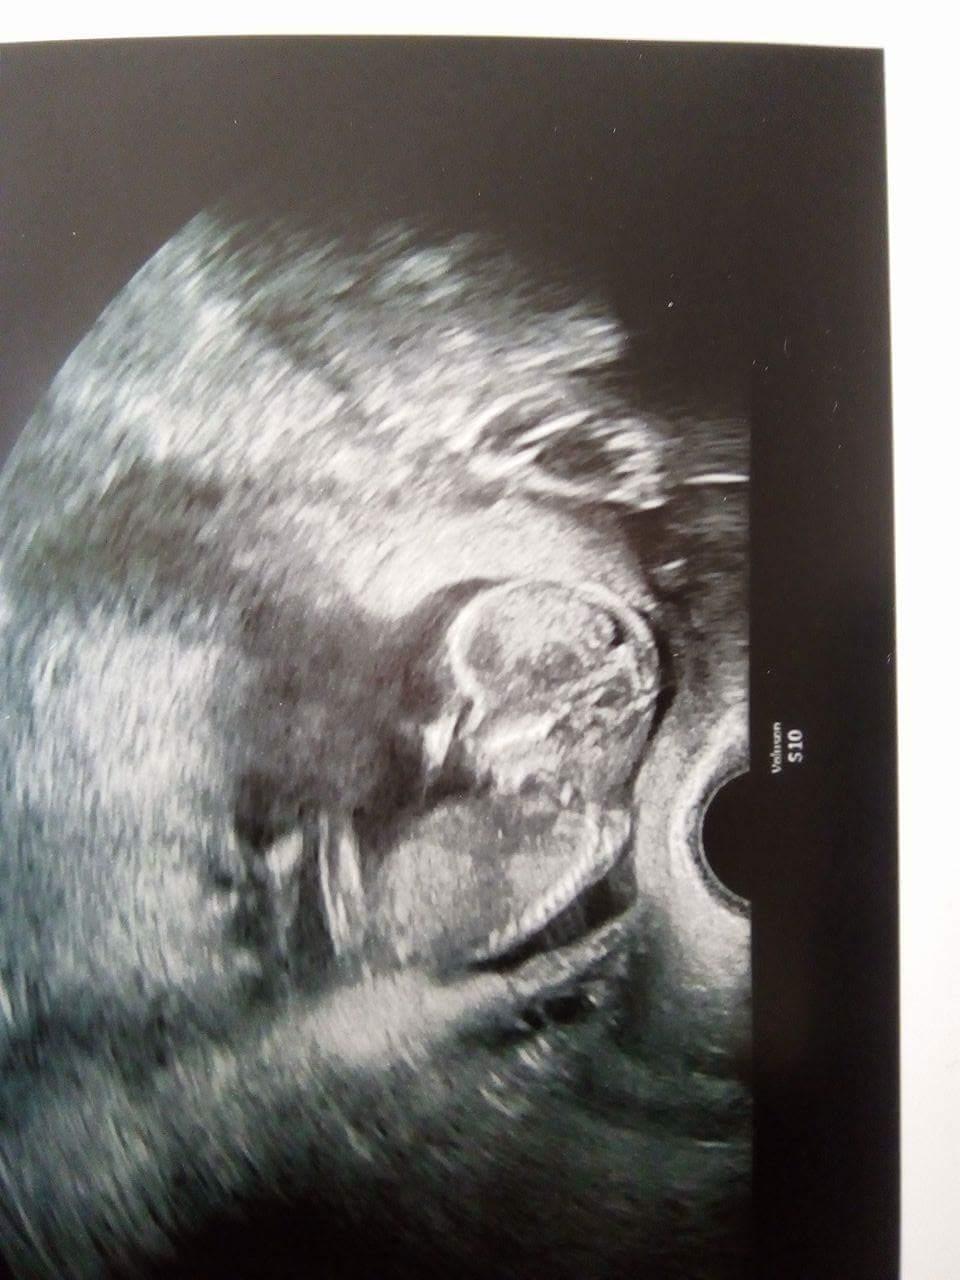

Ja uz jsem 18tt uz ten 15tt co jsem byla na kontrole bylo miminko 🙂 ted uz bude jen tlustsi :D a nevleze se do zaberu